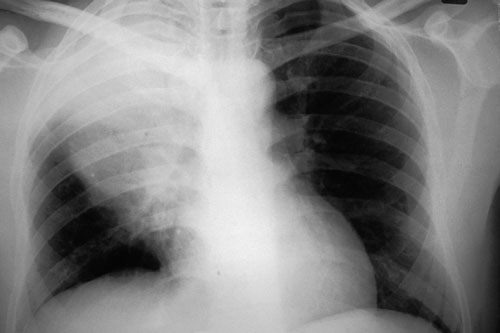

2: Chest x-ray in Streptococcus pneumoniae pneumonia

Chest x-ray is the cardinal investigation in community-acquired pneumonia, but may occasionally be misleading.

At presentation: A 47-year-old smoker presented after just a few hours of rigors and productive cough. Despite clinical signs of right upper zone consolidation, chest x-ray showed only minor abnormalities. Empirical therapy for community-acquired pneumonia was begun.

12 hours later: Chest x-ray showed consolidation in the right upper lobe consistent with the earlier clinical signs. S. pneumoniae was isolated from blood cultures. The patient recovered fully. (X-rays courtesy of Dr Bryan Speed, Fairfield Hospital Historical Collection, Melbourne, VIC.)